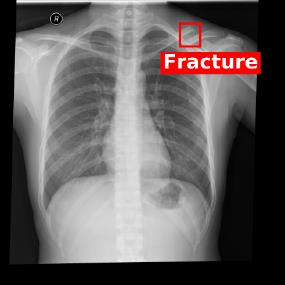

Chest X-ray (CXR) is the most typical diagnostic X-ray examination for screening various thoracic diseases. Automatically localizing lesions from CXR is promising for alleviating radiologists' reading burden. However, CXR datasets are often with massive image-level annotations and scarce lesion-level annotations, and more often, without annotations. Thus far, unifying different supervision granularities to develop thoracic disease detection algorithms has not been comprehensively addressed. In this paper, we present OXnet, the first deep omni-supervised thoracic disease detection network to our best knowledge that uses as much available supervision as possible for CXR diagnosis. We first introduce supervised learning via a one-stage detection model. Then, we inject a global classification head to the detection model and propose dual attention alignment to guide the global gradient to the local detection branch, which enables learning lesion detection from image-level annotations. We also impose intra-class compactness and inter-class separability with global prototype alignment to further enhance the global information learning. Moreover, we leverage a soft focal loss to distill the soft pseudo-labels of unlabeled data generated by a teacher model. Extensive experiments on a large-scale chest X-ray dataset show the proposed OXnet outperforms competitive methods with significant margins. Further, we investigate omni-supervision under various annotation granularities and corroborate OXnet is a promising choice to mitigate the plight of annotation shortage for medical image diagnosis.